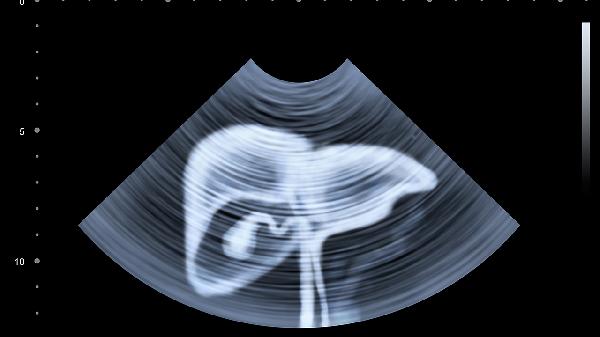

1、影像检查的局限性

CT/MRI只能看到5mm以上的病灶,微小的癌细胞转移就像海底暗流,常规检查难以捕捉。术后3-6个月要做一次特异.性肿瘤标志物检测,这种血液检查能发现影像学看不到的异常。